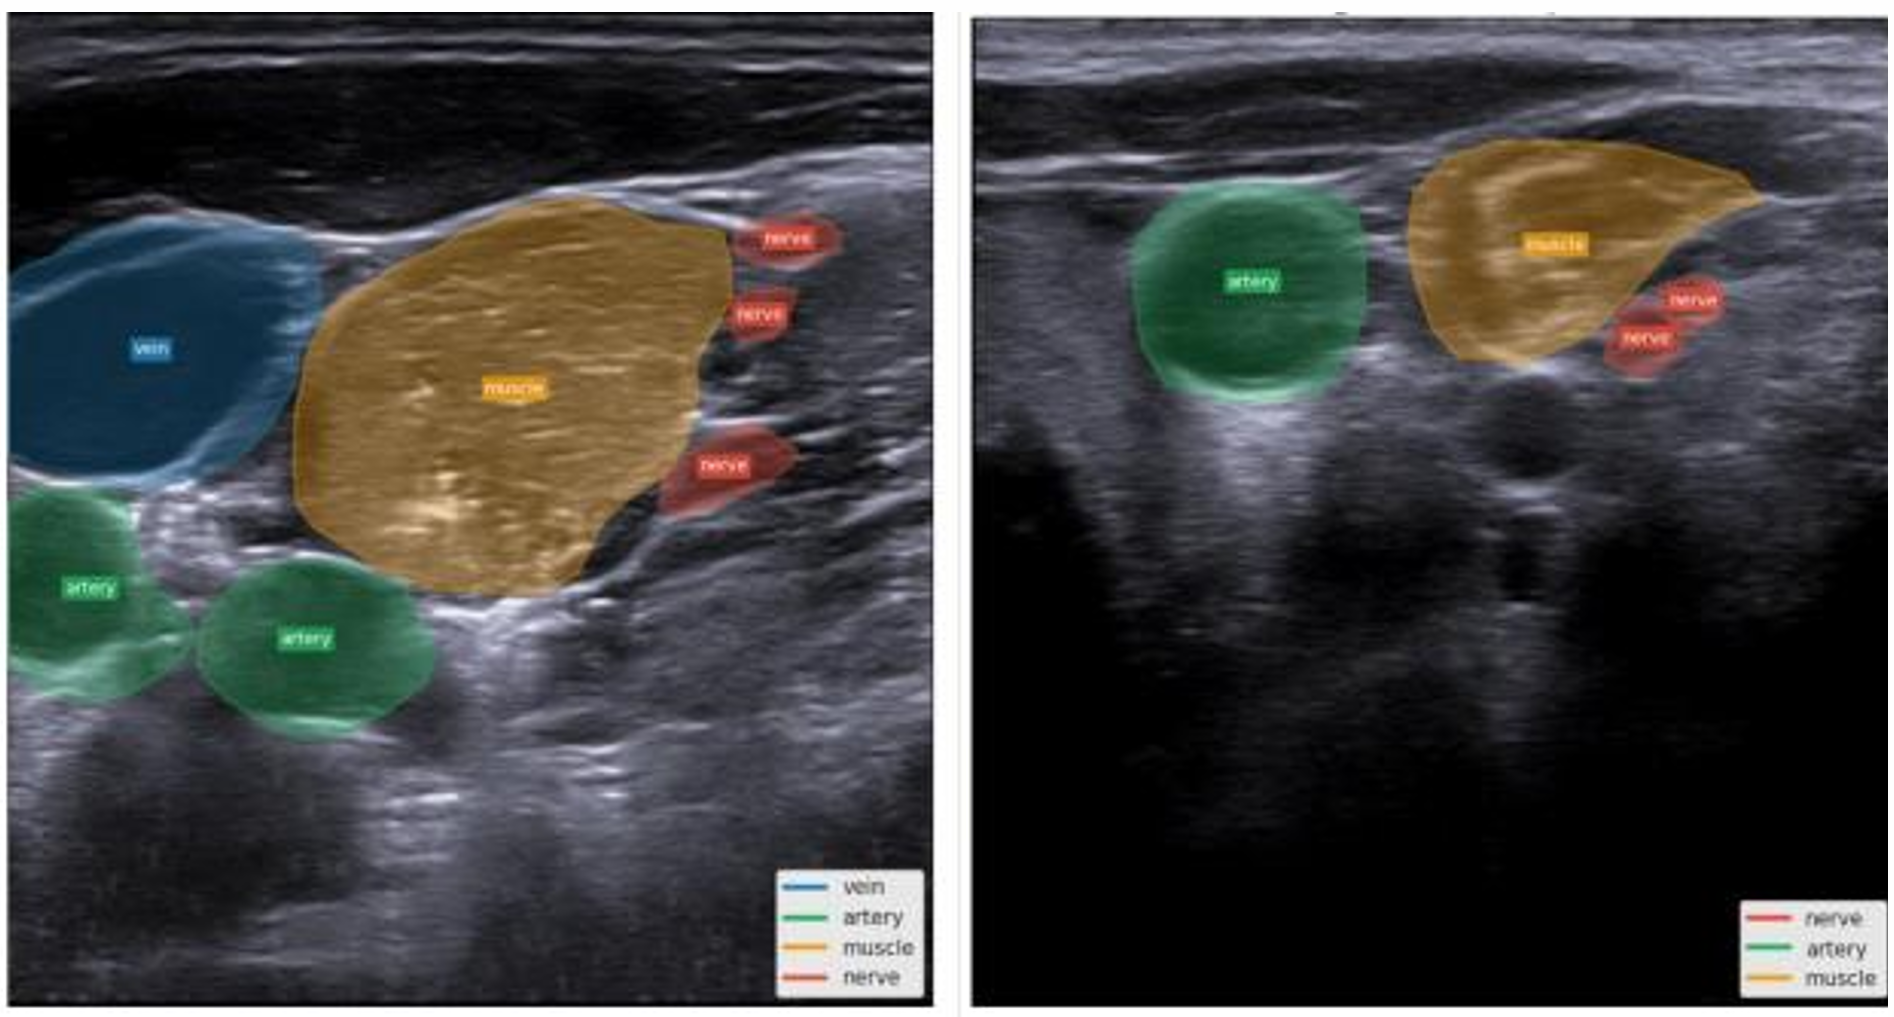

4.2 Multi-landmark Segmentation Challenges

We further extended the segmentation task to include multiple anatomical landmarks: artery, vein, nerve, and muscle. Surprisingly, the addition of these classes led to a substantial drop in the Dice score for the nerve class across all configurations, as shown in Table 2.

Although additional anatomical supervision often aids in contextual understanding, the observed decline suggests that multi-class learning introduces significant complexities for this specific task. The most severe degradation occurred with U1 training, where nerve Dice dropped from 0.274 to 0.107, a 61% relative decrease. U2 and combined datasets showed more modest declines of 11% and 9%, respectively. These challenges may stem from severe class imbalance between the nerve and surrounding muscle tissue, competition for shared representational capacity, and visual similarity between soft tissue structures that introduces ambiguity at nerve boundaries. Qualitative segmentation results are provided in Figure 6, showcasing representative model predictions.

Refer to caption

Figure 6: Representative segmentation results showing input ultrasound images, ground-truth annotations, and model predictions.